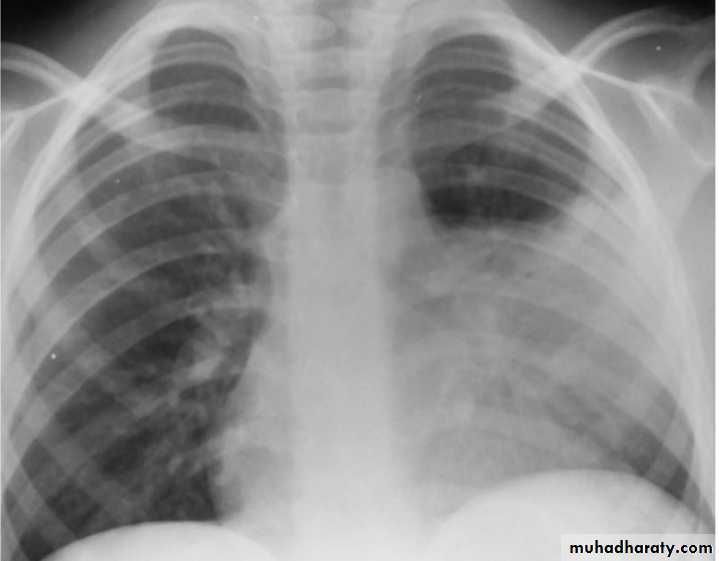

Lobar Pneumonia

Bacterial pneumonia characteristically shows lobar consolidation, or a round pneumonia, with pleural effusion in 10% to 30% of cases.